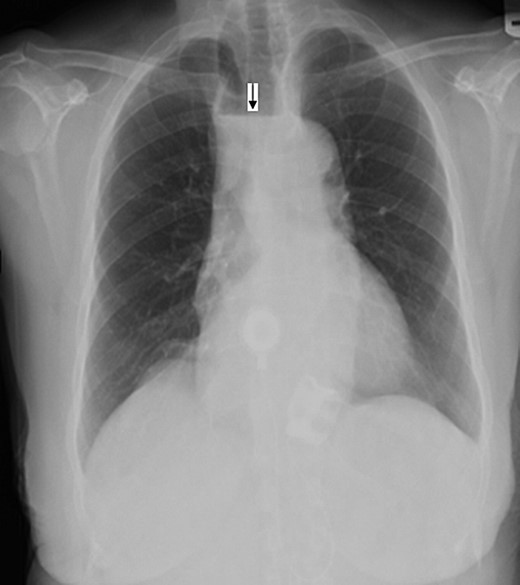

Electrocardiogram was remarkable for Q waves in leads I, aVL and V6. Chest X-ray (CXR) demonstrated a marked esophageal distention with an air fluid level (Figs 1 and 2).

Anterio-posterior CXR views demonstrate the shadow of a dilated esophagus and air fluid level (black arrow).